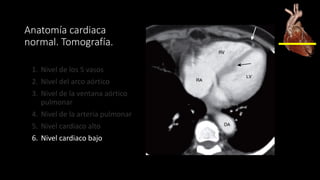

Anatomía cardiaca normal. Tomografía.

1. Nivel de los 5 vasos

2. Nivel del arco aórtico

3. Nivel de la ventana aórtico pulmonar

4. Nivel de la arteria pulmonar

5. Nivel cardiaco alto

6. Nivel cardiaco bajo

Nivel cardiaco bajo

AURÍCULA DERECHA

forma el borde

derecho del corazón.

VENTRÍCULO DERECHO

es anterior, detrás del

esternón y bordes

internos trabeculados.

VENTRÍCULO IZQUIERDO

forma el borde izquierdo del

corazón, tiene pared más

gruesa.

PERICARDIO.

Grosor < 2 mm, delimitado

por la grasa mediastinal

(externa) y grasa epicardica